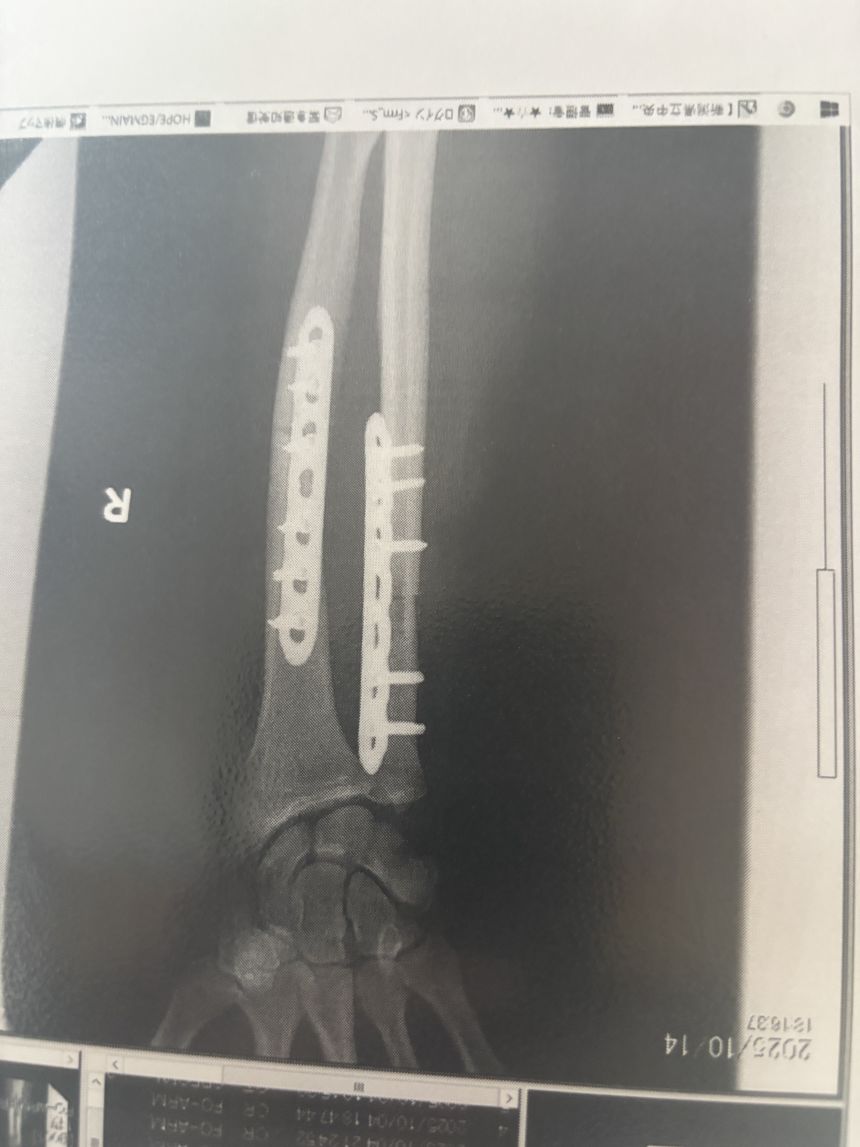

He spoke to CNN from the hospital where he’s been recovering for the past two weeks, having had three surgeries – including a hip graft to cover a chunk of bone that had been bitten off, and the insertion of metal plates into his arm.